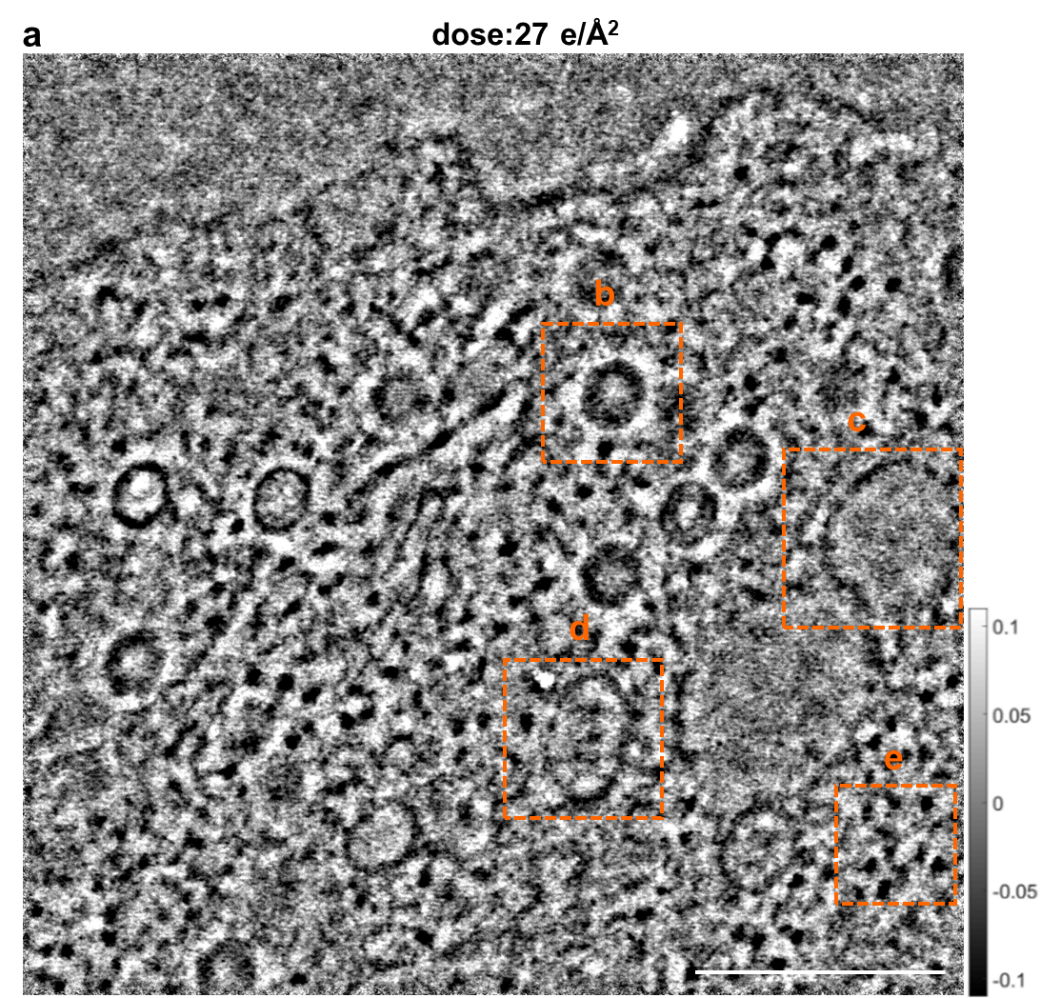

图3所示为腺病毒颗粒感染的细胞在低电子剂量条件27 e/Å2的叠层成像相位图像,成像区域大小为1.14 × 1.14 μm。细胞内亚结构衬度清晰可见,如腺病毒颗粒(b)、空泡(c)、运输小泡(d)、游离ribosome蛋白颗粒(e)等,且这些亚结构的内部结构衬度清晰,如b中的腺病毒颗粒,壳层六边形结构明锐,结构核部遗传物质清晰可见。该结果表明叠层衍射成像可实现生物样品在低电子剂量条件下的微米级大区域成像。

图3 腺病毒颗粒感染的细胞内部微米级区域叠层成像相位图像;图中标尺为300 nm